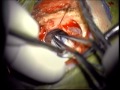

Craniotomies

Microvascular Decompression - Cranial Nerves

Microvascular Decompression for Hemifacial Spasm 2

Microvascular Decompression for Hemifacial Spasm 3

Microvascular Decompression for Hemifacial Spasm 4

Microvascular Decompression for Treatment of Geniculate Neuralgia

Microvascular Decompression for Treatment of Trigeminal Neuralgia 1

Microvascular Decompression for Treatment of Trigeminal Neuralgia 2

Microvascular Decompression for Treatment of Trigeminal Neuralgia 3

Microvascular Decompression for Treatment of Trigeminal Neuralgia 4

Microvascular Decompression of CN7 for Hemifacial Spasm

Retromastoid Craniotomy and Microvascular Decompression of Cranial Nerve 7 for Treatment of Hemifacial Spasm